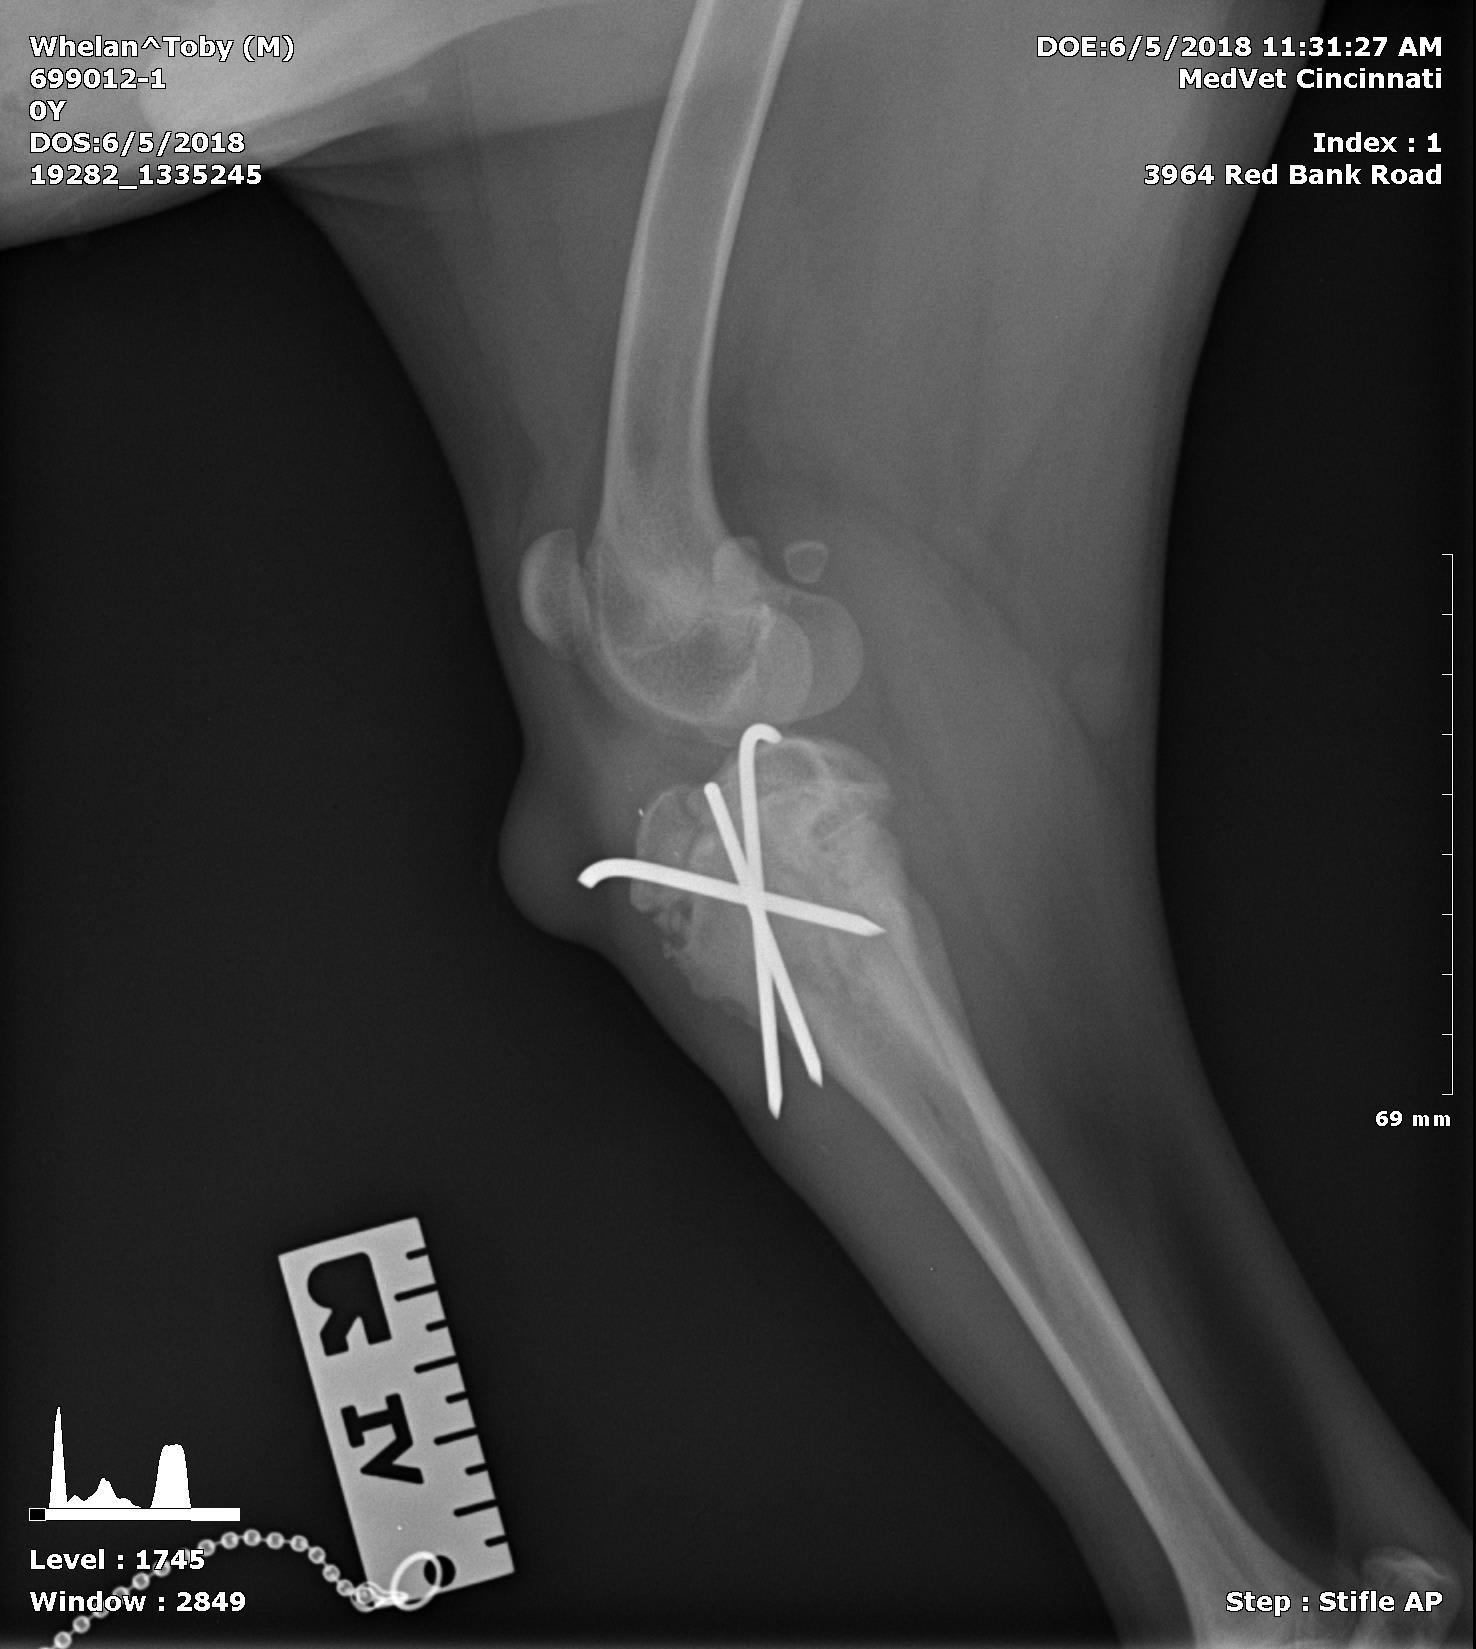

My puppy had surgery on his leg 7 weeks ago after a tibial fracture. They sent me the xrays of the healed bone and it looks like the pins are sticking all the way through the bone and coming out on the other side. The doctor said he is fine and the pins can remain in place for the rest of his life. They look sharp and I can feel a bump where they are through his skin. It looks very strange. Is this normal? The image with three pins is from 2 weeks ago before one of the pins had to be removed.

Hello and thank you for reaching out to Petco Pet Education Center, formerly Petcoach! It is normal for pins to be placed so that they stick out the other cortex (side) of the bone, as this ensures they have a good hold on the fracture fragments to prevent any movement of the fragments. As long as Toby does not develop an infection in his bone around any of the pins, and he is not exhibiting any discomfort from them, he will likely be able to have the pins in for the rest of his life. If you notice that the pins seem to be protruding more than usual, or if Toby is lame/painful on the affected leg, it is possible the pin(s) could have migrated inappropriately and/or could have become infected. This would require a visit to your veterinarian for an exam and repeat x-rays, and potentially surgery to remove the pins. I hope this helps :)